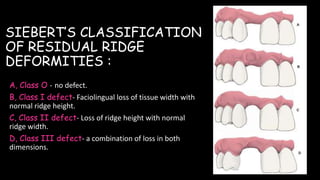

The document discusses pontic design for fixed dental prostheses. It covers pretreatment assessment of residual ridge contours, classifications of ridge deformities, surgical modification techniques, and ideal requirements for pontics. Pontic designs are classified based on their shape and materials. Factors in pontic selection include esthetics and oral hygiene. Common designs for anterior and posterior regions are described, including sanitary, ovate, and saddle pontics. Biological considerations for pontic design involve maintaining the residual ridge, abutment teeth, and supporting tissues.